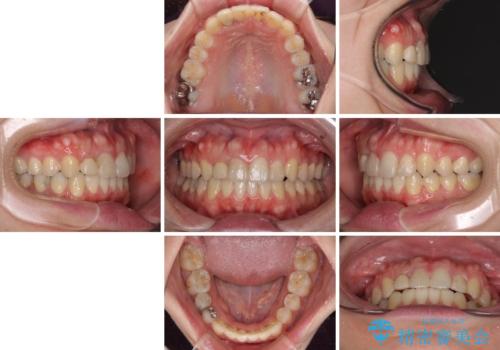

狭い上顎骨を拡大 インビザラインによる非抜歯矯正

- 上下のデコボコと奥歯の咬みにくさを気にして来院された患者様です。

上顎骨の幅が下顎骨よりも小さいので、拡大装置により骨幅を広げて上下関係を改善し、その後インビザラインにて歯並びを整えることとしました。

上下の骨幅を改善したことで、スムーズに歯列矯正を行うことができました。

奥歯の咬み合わせを改善する必要があったため、治療は長期化しましたが、きっちりと仕上げることができました。